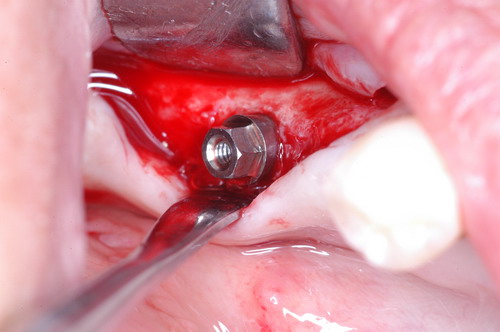

EL USO DEL ARCO GÓTICO DE GYSI , MEDIANTE UNA BÓVEDA PALATINA Y UN APOYO CENTRAL ÚNICO (BO PA YA CU) , EN LA UBICACIÓN DE LA RELACIÓN CÉNTRICA EN UN CASO DE GRAN LAXITUD TENDINOSA CAPSULAR. EL PACIENTE SE PRESENTA A CONSULTA CON UNA EDENTACIÓN PARCIAL, Y GRADO DE MOVILIDAD EXTREMO EN TODAS SUS PIEZAS REMANENTES. SE ESTUDIA EL CASO RADIOGRÁFICA Y CLÍNICAMENTE , Y EL PACIENTE RELATA ESTAR EN ESE ESTADO DESDE HACE MUCHO AÑOS. AL MANIPULAR LA MANDÍBULA EN UN INTENTO DE CONOCER EL ESTADO MUSCULAR DEL SISTEMA, SE OBSERVA UNA GRAN LABILIDAD TENDINOSA CAPSULAR QUE SE MANIFIESTA EN UNA HIPER LAXITUD EN LOS MOVIMIENTOS MANUALMENTE INDUCIDOS DE AMBOS CÓNDILOS DENTRO DE LA CAVIDAD. SE TOMAN IMPRESIONES Y SE MONTA EN UN ARTICULADOR SEMI AJUSTABLE , CORTANDO EN EL YESO LAS PIEZAS QUE SERÁN EXTIRPADAS , CONSERVANDO UNICAMENTE , AMBOS PRIMEROS PREMOLARES INFERIORES , QUE SERÁN UTILIZADOS PARA RETENER MEDIANTE RETENEDORES ELÁSTICOS LA PRÓTESIS INFERIOR , EN LA PRESUNCIÓN DE LA HIPERMOVILIDAD A QUE SERÁ SOMETIDA DADO QUE EN LA GRAN REABSORCIÓN ÓSEA , ES FRECUENTE EL ACERCAMIENTO DE TODAS LAS INSERCIONES MUSCULARES A LA PORCIÓN SUPERIOR DEL REBORDE ÓSEO , LO QUE ATENTARÁ CONTRA LA ESTABILIDAD DE DICHA PRÓTESIS PROVISIONAL. EN UNA PRIMERA SESIÓN CLÍNICO QUIRÚRGICA , SE EXODONCIA TODO EL SECTOR INCISIVO Y CANINO INFERIOR , Y AL OBSERVAR EL REMANENTE ÓSEO CANINO DE AMBOS LADOS , SE IMPLANTA EN FORMA INMEDIATA . TANSCURRIDOS DOS MESES , DONDE LA CICATRIZACIÓN ES ADECUADA , Y LA DINÁMICA MANDIBULAR ACEPTABLE , SE PROCEDE A LA ETAPA QUIRÚRGICA IMPLANTARIA MEDIANTE IMPLANTES SEMI SUMERGIDOS, CON ALGUNAS ZONAS DE REGENERCIÓN ÓSEA GUIADA FIG17 FIG18 FIG19 FIG26 DURANTE LA ETAPA DE CICATRIZACIÓN DE ESTE NUEVO ABORDAJE QUIRÚRGICO , SE ENDODONCIAN AMBOS PREMOLARES INFERIORES CONSERVADOS , LOS QUE EN UN FUTURO , CUANDO YA NO SIRVAN PARA RETENER LA PRÓTESIS REMOVIBLE PROVISORIA INFERIOR , SERÁN CORTADOS COMO RESERVA DE CAPITAL ÓSEO O BIEN COMO ELEMENTO RETENEDOR ANTE CUALQUIER TIPO DE INCIDENCIA IMPLANTARIA. ABORDAMOS LA ETAPA PRIMARIA PROTÉTICA , UNA VEZ TRANSCURRIDOS TRES MESES, MEDIANTE LA UTILIZACIÓN DE CUBETAS INDIVIDUALES , A LAS QUE REALIZAMOS UN RECORTE MUSCULAR EN BASE A STENS VERDE , COMO SI DE UNA PRÓTESIS COMPLETA SE TRATARA. DE ESE MONTAJE OBTENEMOS DOS RODETES DE METACRILATO , PERFECTAMENTE ADAPTADOS A LOS MODELOS FUNCIONALES , A LOS QUE LES OTORGAMOS LA PLANIMETRÍA DERIVADA DEL PARALELISMO CON EL PLANO DE FRANKFURT , Y UNA ALTURA (DV) QUE RESULTA DE LOS MÉTODOS MÉTRICOS DE DIMENSIÓN VERTICAL… Y QUE NOS SERVIRAN ADEMÁS DE TOMAR UNA NUEVA IMPRESIÓN FUNCIONAL MEDIANTE RECORTE MUSCULAR , PARA ADAPTAR UN DISPOSITIVO CONSISENTE EN UNA BÓVEDA PALATINA SUPERIOR , Y UN TORNILLO CENTRAL INFERIOR , LOS QUE DESPUÉS DE UN ENTRENAMIENTO ADECUADO DEL ENFERMO , NOS PERMITIRÁ REPRODUCIR EN EL BÓVEDA , EL ARCO GÓTICO DE GYSI , ENCONTRANDO DE ESTA MANERA LA OCLUSIÓN EN RELACIÓN CÉNTRICA. ACTUALMENTE ESTE MÉTODO HA SIDO RECREADO MEDIANTE LA DENOMINACIÓN DE: FIG50 FIG51 FIG52 OBTENIDO EL DIBUJO DEL ARCO GÓTICO , INSINUAMOS EN EL VÉRTICE DEL MISMO UNA PERFORACIÓN QUE FIJARÁ LA PUNTA DEL TORNILLO EN ESA POSICIÓN: RELACIÓN CÉNTICA FIG55 FIG56 FIG57 CON ESTOS PARÁMETROS SE CONSTRUYEN DOS SOBREDENTADURAS ABROCHADAS EN RÓTULAS SUPRA IMPLANTES , QUE LE OTORGAN FIJACIÓN SUFICIENTE , DANDO A LA OCLUSIÓN TODOS LOS ELEMENTOS DE UNA: OCLUSIÓN MUTUAMENTE COMPARTIDA, REFERENCIA II CON UN ESQUEMA OCLUSAL DE : FUNCIÓN DE GRUPO BILATERAL POSTERIOR DE ACCIÓN CANINA DESPUÉS DE LAS REVISIONES PERTINENTES A LA SEMANA , EL MES Y LOS SEIS MESES DE TERMINADA LA REHABILITACIÓN , SE CITA AL ENFERMO PARA UN NUEVO CONTROL AL AÑO Y MEDIO Y SE OBSERVA UNA PERFECTA SITUACIÓN TISULAR , CLINICA Y RADIOGRAFICAMENTE CONTROLADA , Y ADEMÁS LA PERMANENCIA DEL MISMO ESQUEMA OCLUSAL OTORGADO DESDE EL PRINCIPIO. SE CONTROLA RADIOGRAFICAMENTE Y SE DA EL ALTA DEFINITIVA RECOMENDANDO EL CONTROL DOS VECES AL AÑO. REFERENCIAS: I : II. : III: